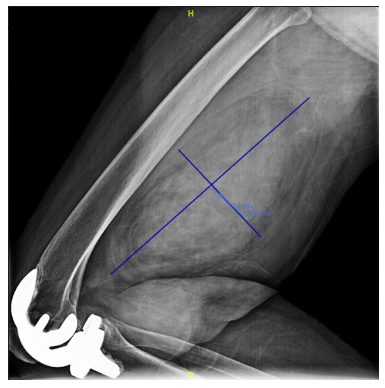

Radiographic imaging is used to help form a diagnosis. These include X-Ray, MRI, CT and Bone Scans

An example of an MRI is shown.